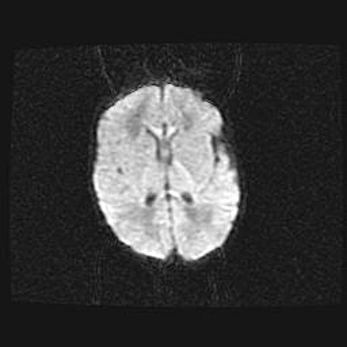

Церебральная ишемия II.

Возраст: 5 дней

Вес: 3400 г

Пол: женский

Окружность головы: 35 см

Срок гестации: 39 недель

Церебральная ишемия – это заболевание, характеризующееся недостаточностью (гипоксией) либо полным прекращением (аноксией) снабжения мозга кислородом по причине закупорки одного или нескольких сосудов. Это приводит к  что метаболическим расстройствам различной степени тяжести в тканях головного мозга, развитию коагуляционных некрозов и гибели нейронов.